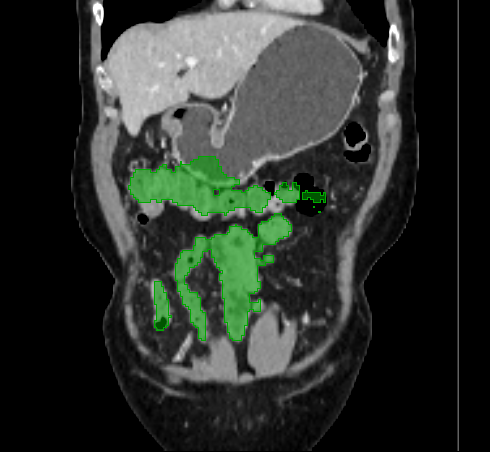

3.2 Qualitative Evaluation

Figure 3 shows example segmentation results in 3D. The result corresponding to ‘feat. & out. level DA’ in Table 1 is compared to ours. We note that the only difference between them is whether the feature disentanglement is involved for the domain adaptation, thus could show its effectiveness. Fewer errors are observed for the proposed method. We believe this is because the proposed method explicitly concentrates on the features more transferable across the datasets, the non-intensity features in this work, by disentangling those features and applying adversarial learning directly to them during the adaptation process. Example reconstruction results from the auto-encoding architecture as well as segmentation results in coronal view can be found in supplementary material.